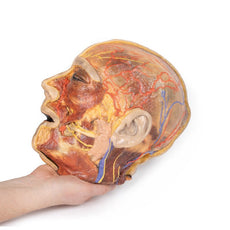

The head and neck of the specimen provides views of both superficial and deep structures in the region. The calotte has been removed ~2cm superior to the orbits to expose the brain in relation to the endocranial cavity. The transverse section through the cerebrum demonstrates the relation of the grey matter cortex to the white matter medulla, as well as the lateral ventricles with a small amount of choroid plexus visible in the base of both spaces. The skin and superficial fascia on the right side has been retained and false-coloured to display the angiosomes of the face and posterior neck. On the left side, the superficial tissues have been dissected to expose the muscles of facial expression, muscles of mastication, and deeper structures of the infratemporal fossa including the lingual nerve, terminal branches of the external carotid artery into the superficial temporal and maxillary arteries.

The head and neck of the specimen provides views of both superficial and deep structures in the region. The calotte has been removed ~2cm superior to the orbits to expose the brain in relation to the endocranial cavity. The transverse section through the cerebrum demonstrates the relation of the grey matter cortex to the white matter medulla, as well as the lateral ventricles with a small amount of choroid plexus visible in the base of both spaces. The skin and superficial fascia on the right side has been retained and false-coloured to display the angiosomes of the face and posterior neck. On the left side, the superficial tissues have been dissected to expose the muscles of facial expression, muscles of mastication, and deeper structures of the infratemporal fossa including the lingual nerve, terminal branches of the external carotid artery into the superficial temporal and maxillary arteries.